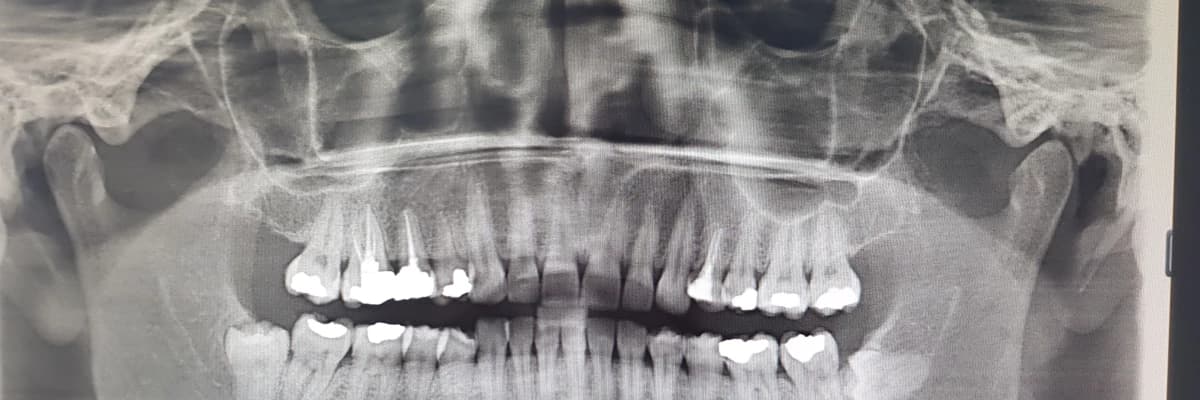

Bilindiği gibi 20 yaş dişleri diş hekimliği pratiğindeki adıyla 8 numaralı dişler hayatın 2.dekatında ağız ortamına sürmeye başlayan dişlerdir. Bu dişler çeşitli gelişim bozuklukları, patolojiler, sistemik hastalıklar ve lokal nedenlerden dolayı ağız ortamına süremezler ve gömülü kalırlar. Yaygın olarak üst çene ve alt çene 20 yaş dişleri olmak üzere ağızda köpek dişi dediğimiz kanin dişleride gömülü kalabilen dişlerdendir.Normal seyrinde ağız ortamına sürmeyen , alveol kemiği dediğimiz çene kemiği içinde gömülü kalan dişler genel görüşe göre çıkarılmalıdır.Fakat her 20 yaş dişi gömülü kalmamaktadır. Ağız ortamına istediğimiz şekilde sürmekte ve yeme ve içme fonksiyonuna katılmaktadır.Bu durumlarda çekilmesi gerekmemekte bilakis ağızda kalması istenmektedir.

Bazı hastalarda 20 yaş dişleri 20 yaşına kadar çıkma eğilimi gösterirken bu süre 25 yaşına kadar uzayabilmektedir.Gömülü dişlerin çekimini gerektiren çeşitli sebepler bulunmaktadır. Bu sebepler arasında; ağızda görünen fakat istediğimiz pozisyonda süremeyen yarı gömülü dişlerin dişetine baskı yaparak orada perikoronit dediğimiz iltihabi durumu meydana getirmesi, komşu dişe baskı yaparak kök rezorpsiyonu(erimesi) yapması, gömülü diş etrafında radyolojik muayene ile saptanan lezyonların olması, bir tam protez yaptıracak hastaya engel olması vb. olarak sayılabilir. İşte bu gibi durumlarda doktorunuz gerekli gördüğü takdirde gömülü kalan dişleriniz çekilebilmektedir. Fakat ilerleyen yaşlarda, şeker, tansiyon, kanama problemleri, kemik hastalıkları sistemik hastalıklarda çene cerrahisi uzmanına danışmakta fayda vardır.